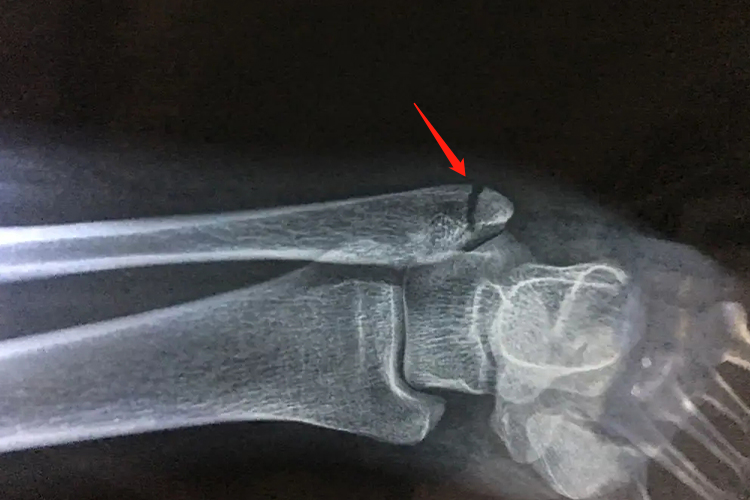

左腓骨外踝骨折表现为左侧腓骨远端外踝关节处出现骨组织完整性断裂,X线可见有骨折裂缝,多伴有踝关节韧带损伤,局部有瘀血、肿胀、疼痛,有明显活动受限,触诊会发现骨损伤点的压痛比外侧韧带处明显。